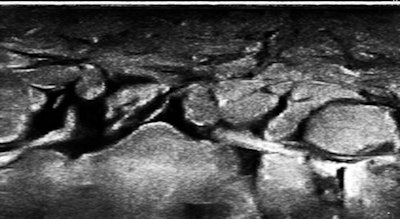

So, of course, we had a look at the thoracic duct, which had an abnormal appearance (image below). The technique of visualizing the terminal portion of the thoracic duct, adjacent to the left jugular vein, was published by Seeger et al (Radiology, September 2009, Vol. 252:3, pp. 897-904).